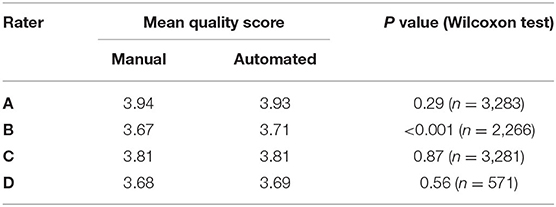

We subsequently investigated the distribution of the scores for each rater (Figure 3). We observed that the difference between the mean quality scores assigned to each segmentation method was not statistically significant for most evaluators, except for rater B (Table 1). The distribution of quality scores after excluding rater B, showed no significant difference between the two methods (OR (95% CI) = 1.05 (0.94–1.17); p = 0.40).

Figure 3. The distribution of quality scores for each rater for both sources of contours: manual (blue) and automated (orange) segmentation.

Table 1. Comparison of the mean quality score for manual and automated contours, and their corresponding Wilcoxon test p-value for statistical significance, for each rater.